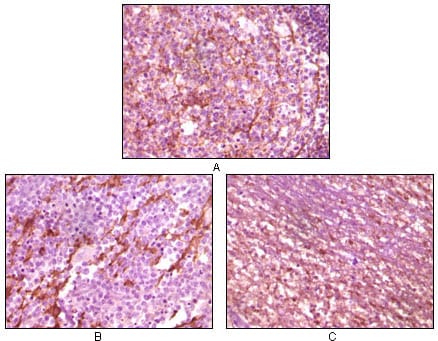

分类: 科研抗体货号: 20059别名: BFGF; FGFB; HBGF-2; FGF2应用: IHC反应种属: Human

分类: 科研抗体货号: 20073别名: HTK; MYK1; TYRO11应用: IHC反应种属: Human